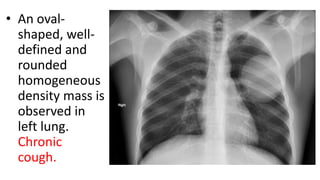

• Uncomplicat

ed and intact,

or

unperforated

, cysts may

be diagnosed

as round or

oval-shaped

lesions with

regular

fine margins.

• An oval-

shaped, well-

defined and

rounded

homogeneous

density mass is

observed in

left lung.

Chronic

cough.